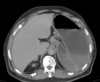

Paciente feminina, 48 anos, hipertensa e diabética tipo 2, com diagnóstico de neoplasia colorretal, submetida a tratamento cirúrgico e quimioterapia adjuvante há 8 meses. Durante o tratamento quimioterápico, apresentou importante perda ponderal, sendo seu peso atual de apenas 44 kg. Comparece ao pronto-socorro com queixa de epigastralgia, sensação de plenitude pós-prandial, saciedade precoce, náuseas e vômitos biliosos. Esses sintomas eram esporádicos, porém tornaram-se mais intensos nos últimos dias. Ao exame físico: descorada ++/4, desidratada ++/4, eupneica, afebril. FC: 98 bpm, PA: 110 x 60 mmHg, FR: 18 irpm. Abdome escavado, flácido, pouco doloroso à palpação e com distensão no andar superior, sem massas palpáveis, RHA presentes. Realizada passagem de sonda nasogástrica com saída de grande volume de estase gástrica. Exames laboratoriais: Hb: 9,5 g/dL; leuco: 10,50 mil/mm³ (sem desvio à esquerda); PCR: 10 mg/dL; K: 3,2 mmol/L, creatinina: 1,3 mg/dL; ureia: 40 mg/dL, glicemia: 163 mg/dL. Foi realizada tomografia contrastada de abdome (imagem a seguir). Em relação ao caso, qual é a principal hipótese diagnóstica?

Sindrome de wilkie, obstruindo o duodeno

O que é a sindrome de wilkie?

compressão da terceira porção do duodeno devido ao estreitamento do espaço entre a **artéria mesentérica superior** e a aorta